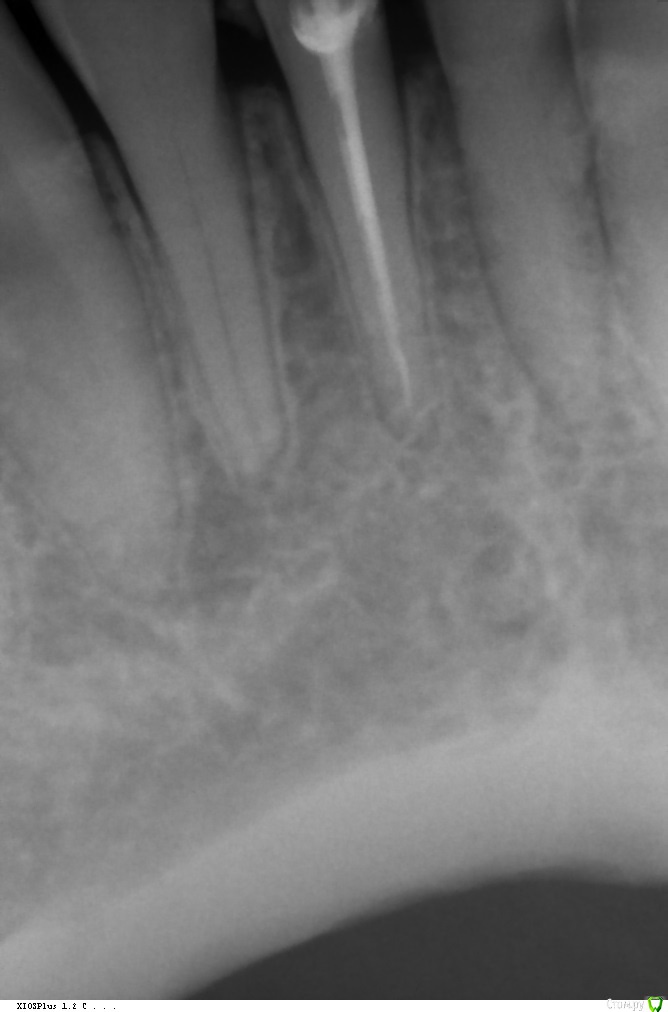

orlova Опубликовано 14 августа, 2016 Поделиться Опубликовано 14 августа, 2016 Доброго времени суток.В результате травмы в 2011г потеряла больше половины 41 зуба(нерв удалён)Обратилась в местную частную стоматологию, там мне заново запломбировали канал и вот сейчас хотят поставить стекловолоконный штифт и безметалл E-max.Но доктора как-то не были уверенны в том, что действительно нужно делать и что выбрать.И ещё один момент: доктор сказал, что у меня слишком маленький корень и из-за этого нужно ставить стекловолоконный штифт, но я читала, что как раз таки наоборот не рекомендуют ставить штифт, если корень зуба маленький.По этой причине пошла в другую стоматологию, где хотят сделать всё совершенно по-другому: не ставить штифт, а поставить вкладку и металлокерамическую коронку (цена больше 25к).Что посоветуете и как прокомментируете план лечения? Я в полнейшей растерянности. Хочется к 1 сентября быть уже с зубом.Спасибо! Ссылка на комментарий

dok1 Опубликовано 14 августа, 2016 Поделиться Опубликовано 14 августа, 2016 42 - кажется какой-то периапикальный процесс нехороший идёт. 1 Ссылка на комментарий